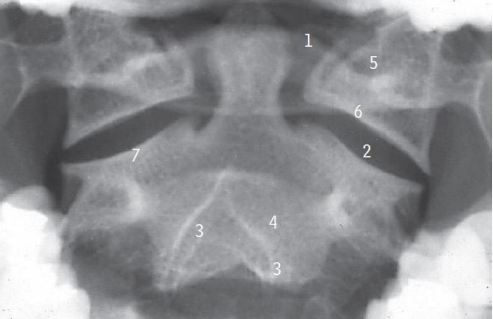

Intraoral view

Arch of altlas.

Atlanto-axial joint.

Bifid spinal process.

Body of axis.

Lateral mass of axis

Inferior articular process; Superior articular process

What are the abnormal signs in this radiograph

Alignment (distance between dens and lateral masses of C1 not equal.

Soft tissue swelling -